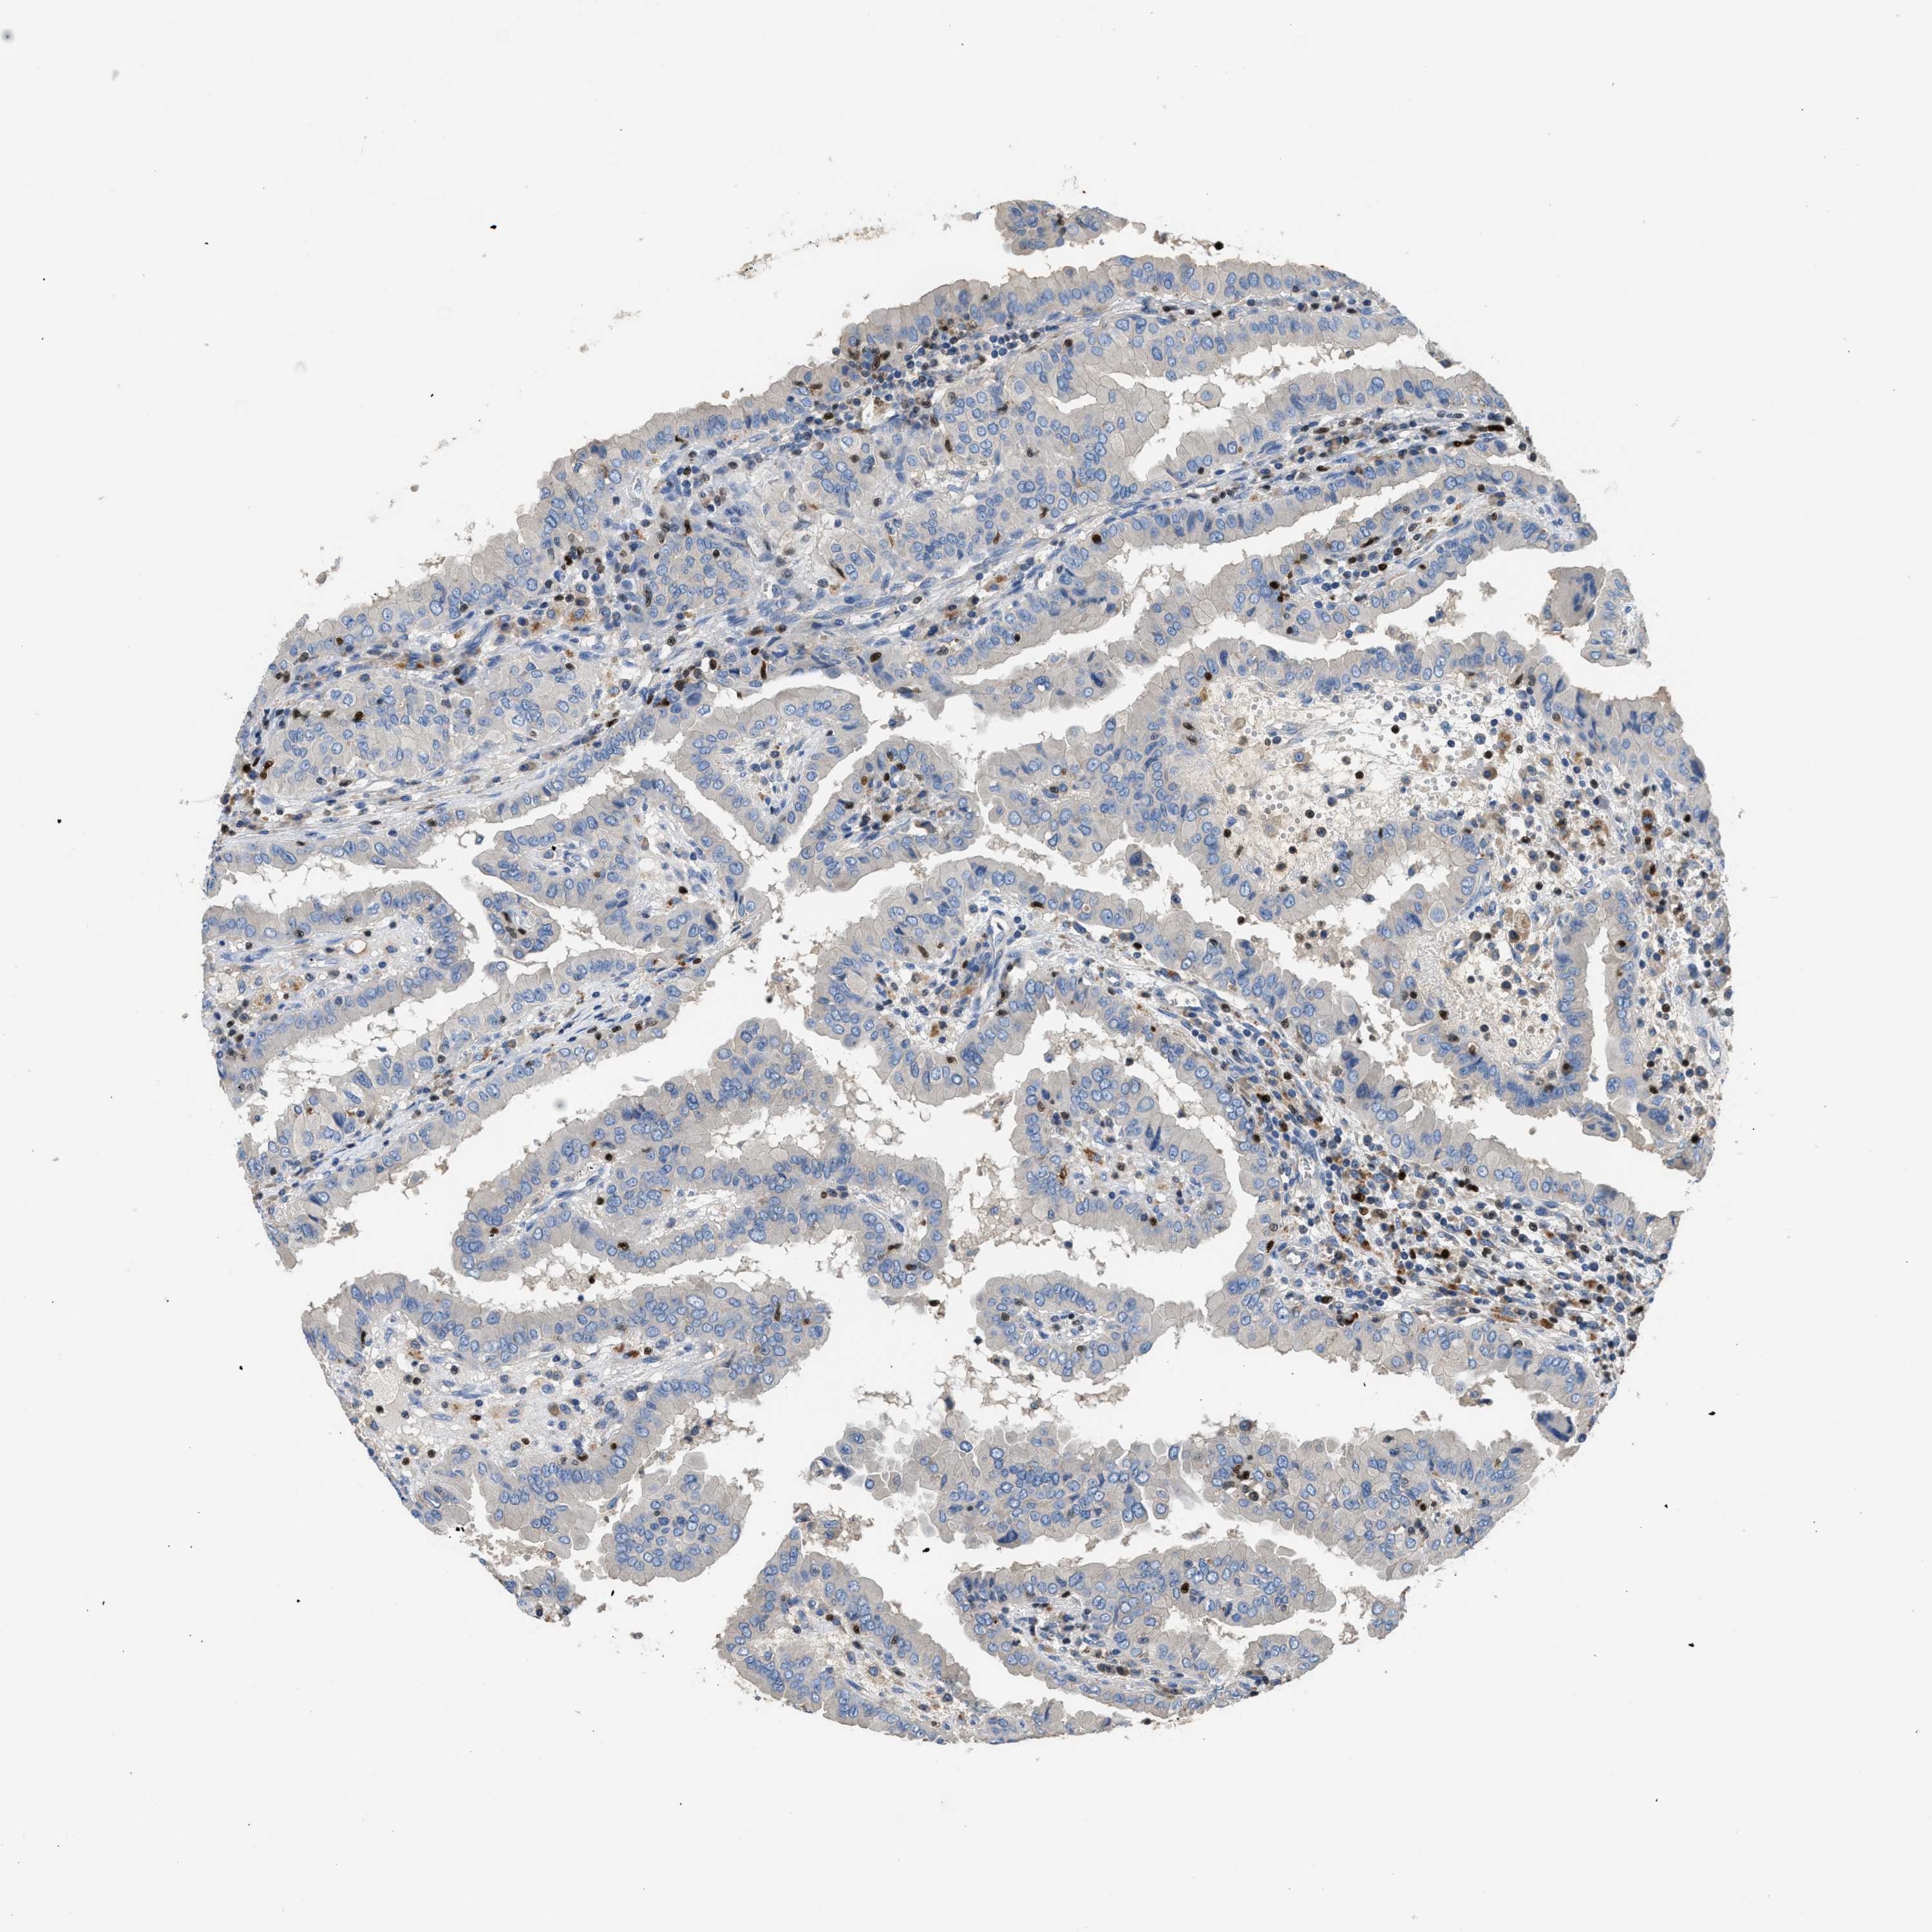

THYROID CANCER - Protein expressioni

A mouse-over function shows sample information and annotation data. Click on an image to view it in a full screen mode. Samples can be filtered based on level of antibody staining by selecting one or several of the following categories: high, medium, low and not detected. The assay and annotation is described here.

Note that samples used for immunohistochemistry by the Human Protein Atlas do not correspond to samples in the TCGA dataset.

Antibody stainingi

Antibody staining in the annotated cell types in the current human tissue is reported as not detected, low, medium, or high, based on conventional immunohistochemistry profiling in selected tissues. This score is based on the combination of the staining intensity and fraction of stained cells.

Each image is clickable and will lead to virtual microscopy that enables deeper exploration of all samples and also displays staining intensity scores, fraction scores and subcellular localization as well as patient and tissue information for each sample.

Antibody HPA018322

Staining

High

Medium

Low

Not detected

Intensity

Strong

Moderate

Weak

Negative

Quantity

>75%

75%-25%

<25%

None

Location

Nuclear

Cytoplasmic/membranous

Cytoplasmic/membranous,nuclear

Papillary adenocarcinoma, NOS

Follicular adenoma carcinoma, NOS